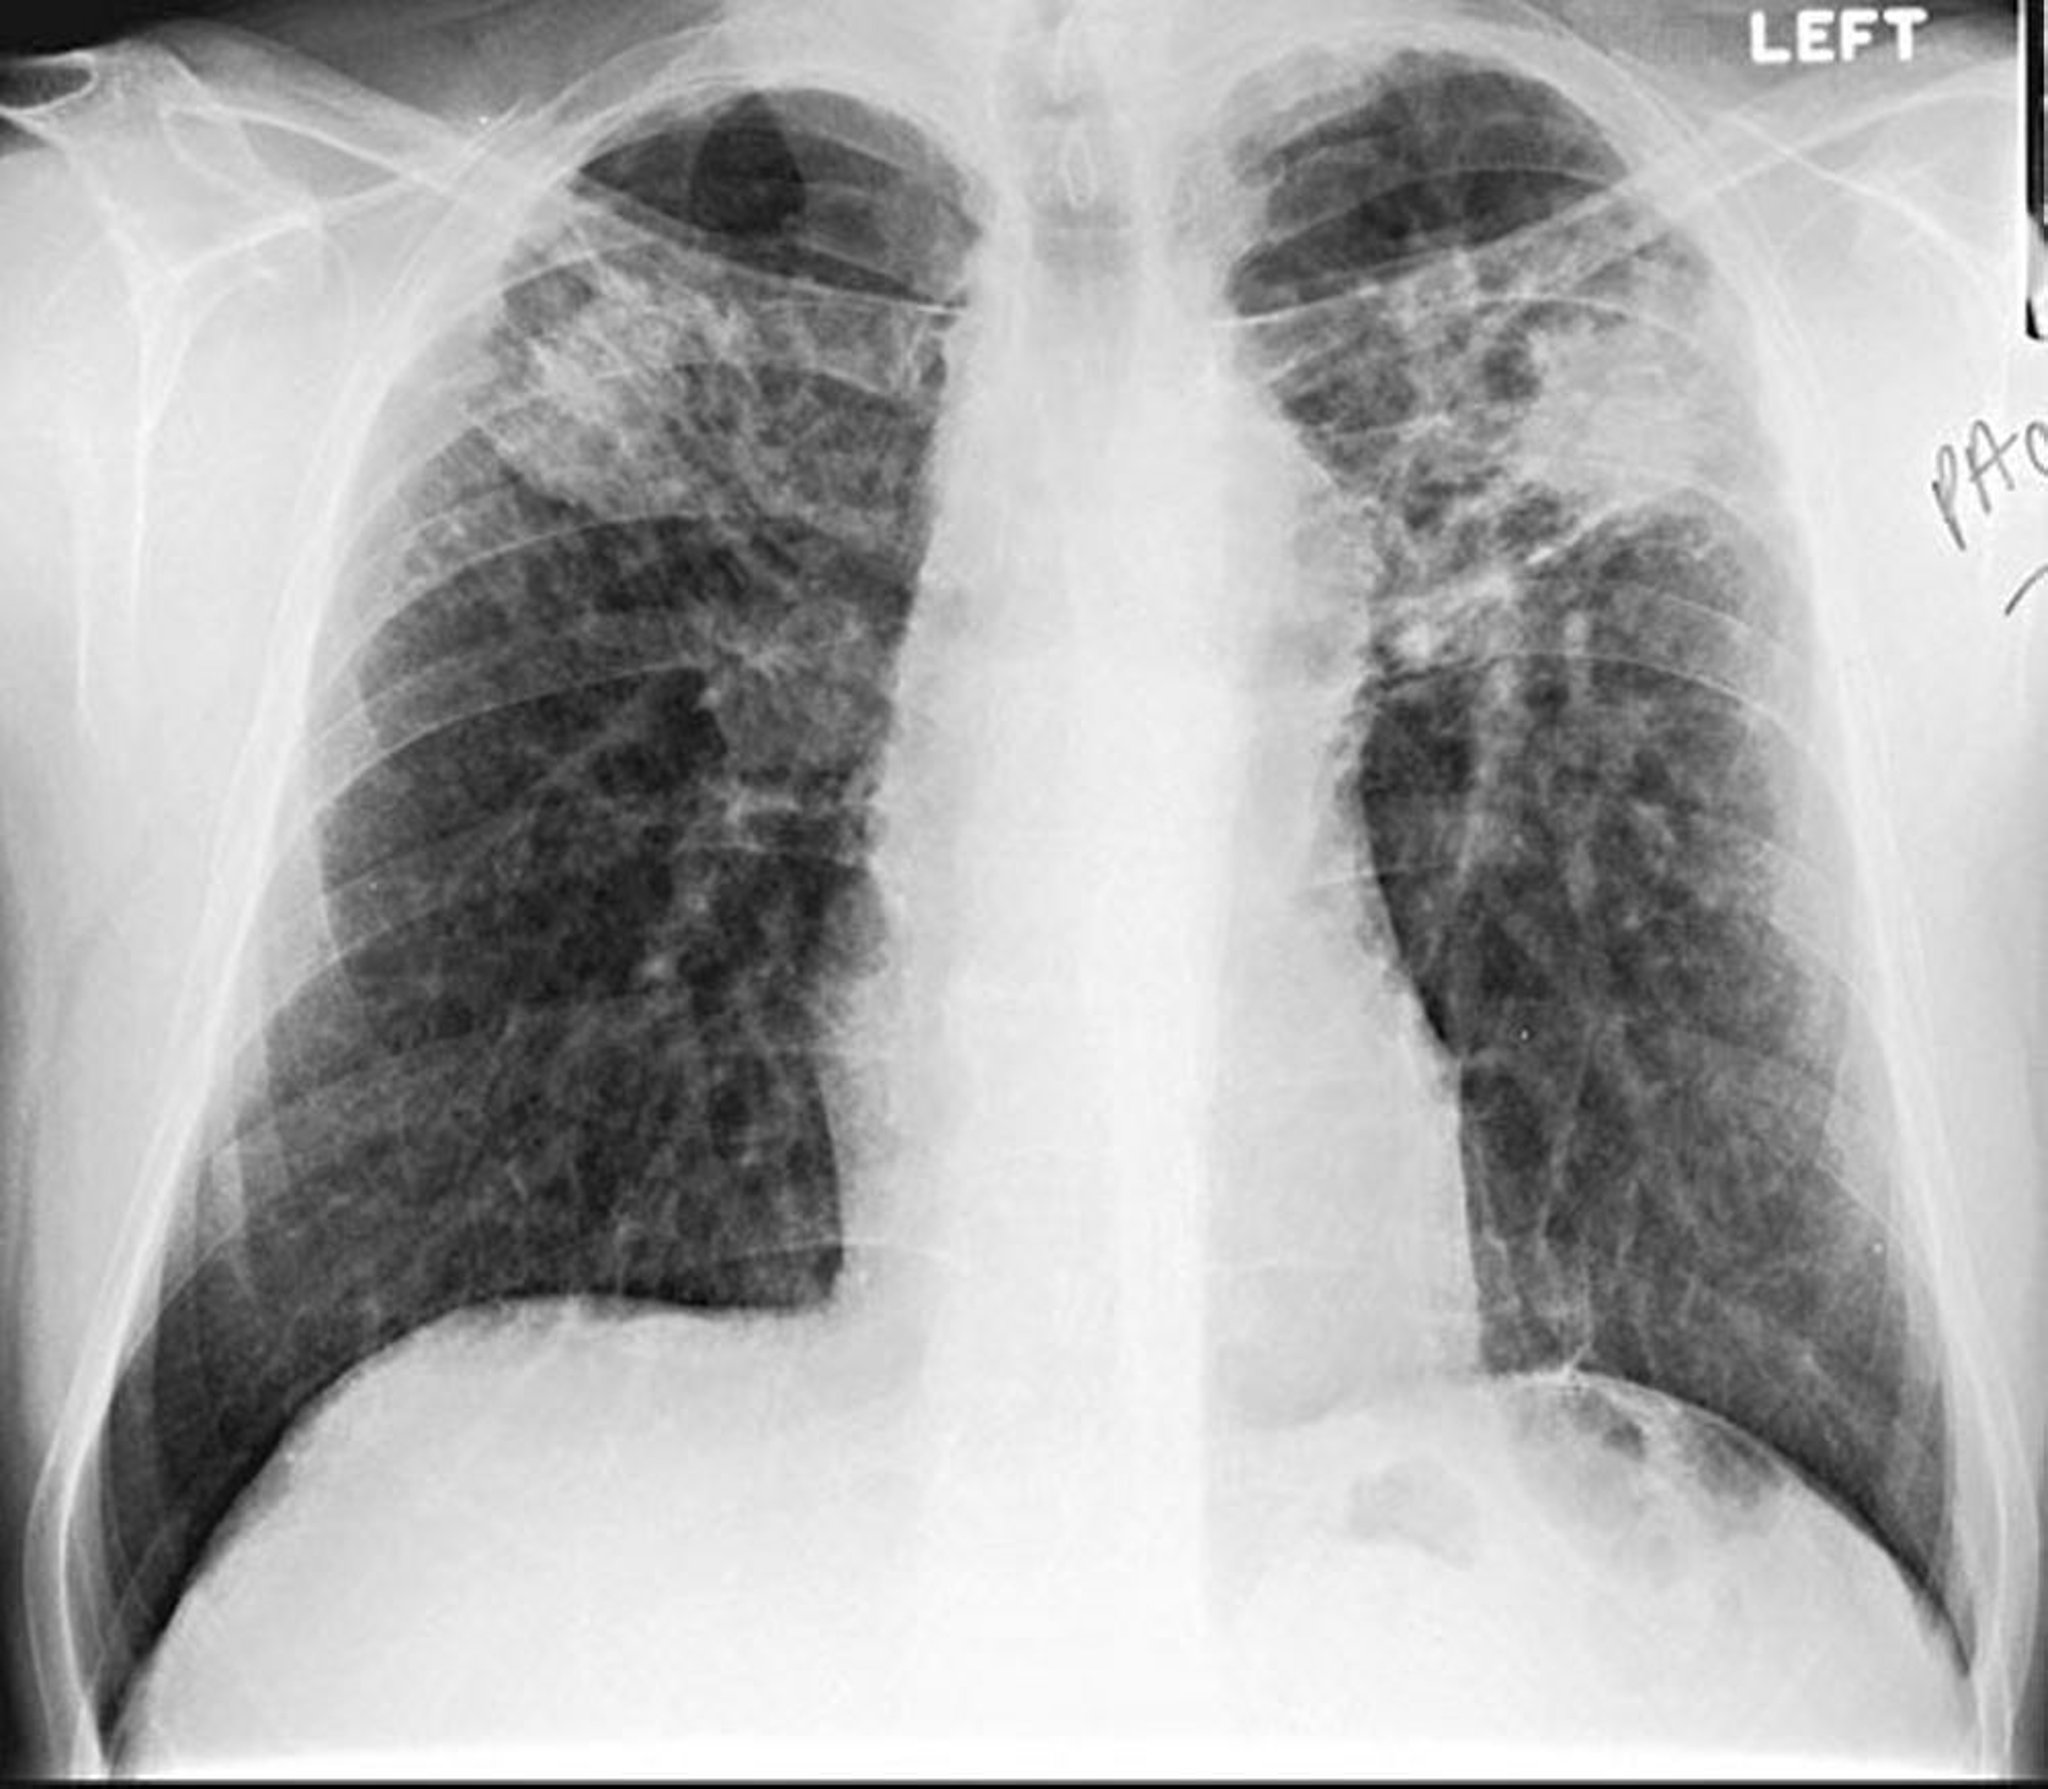

Silikose - Konglomerat

Image courtesy of David W. Cugell, MD.